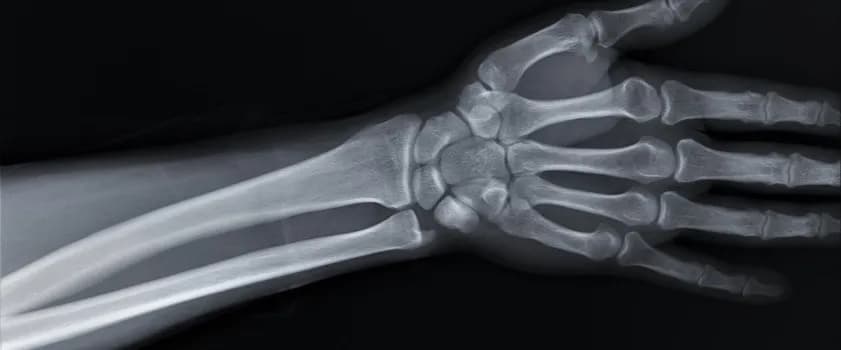

Czy złamana ręka puchnie? Tak, to normalne zjawisko. Obrzęk po złamaniu ręki to naturalna reakcja organizmu na uraz. Gdy dochodzi do złamania, ciało natychmiast rozpoczyna proces gojenia, co wiąże się z napływem płynów i komórek odpornościowych do uszkodzonego obszaru.

Ta reakcja obronna prowadzi do spuchnięcia ręki po złamaniu. Choć może być uciążliwa, opuchlizna złamanej ręki jest kluczowa dla procesu regeneracji tkanek i kości.